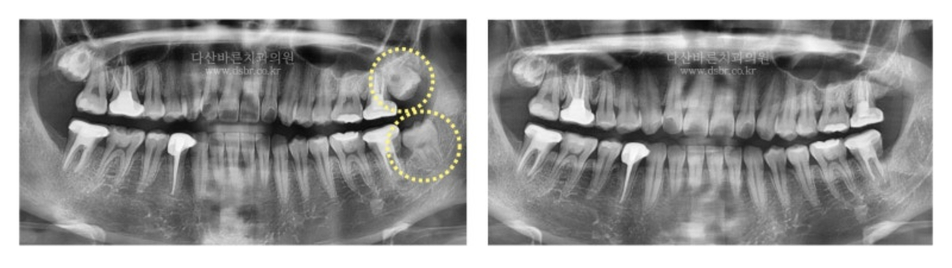

Bệnh nhân này đã nhổ một chiếc răng khôn hàm trên và một chiếc răng khôn hàm dưới.

Răng khôn mọc tương đối thẳng và mức độ mọc ngầm không sâu lắm.

Tuy nhiên, do khoảng cách giữa hàm dưới và răng hàm cuối cùng hẹp,

răng khôn hơi bị nướu che phủ nên đây là trường hợp có thể

nhổ hết răng cùng lúc chỉ bằng một đường rạch nhỏ ở nướu.